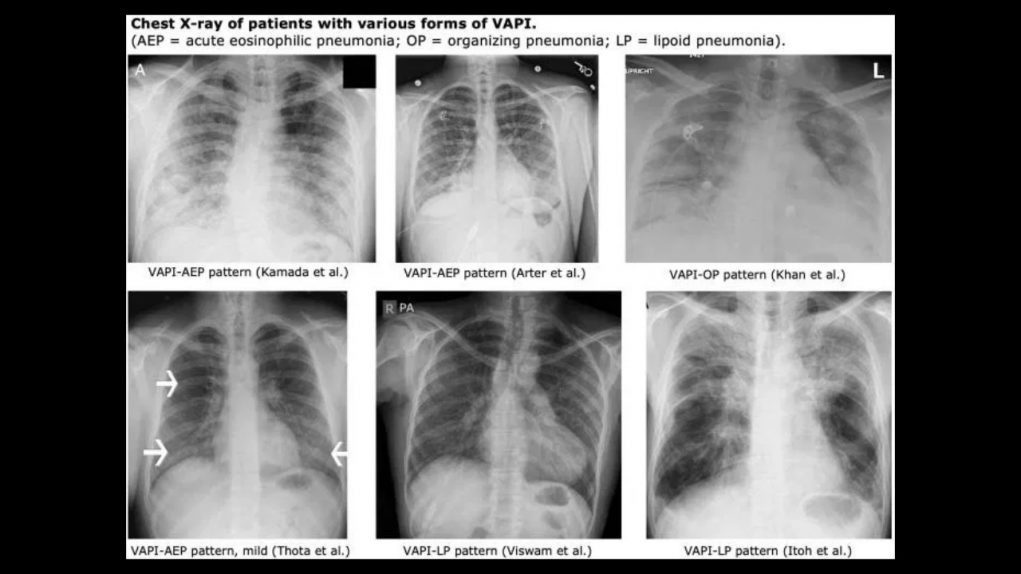

For a while there at the last half of 2019, vaping-associated lung illness was the biggest health story in the news. It was quickly tied – partly by us – to black market / counterfeit / unlicensed THC vape cartridges. Since then we’ve gone on reporting on the issue, trying to help users sort out what’s licensed, what’s tested, and what’s bunk.

Meanwhile, Vaping-associated pulmonary injury (VAPI) has been eclipsed by an even BIGGER health news story in the ongoing COVID-19 CoronaVirus global pandemic. It is no exaggeration to say that the pandemic has completely reshaped our world, impacting everyone’s lives on many fronts. If anything, the cannabis industry doesn’t have much room to complain compared to some other industries. Dispensaries have the status of “essential business” due to medical needs, so if anything the cannabis industry has proved surprisingly resilient.

However, just because the media has stopped talking about VAPI doesn’t mean it’s gone away. As we’ve been keeping an eye on the situation here at Dab Connection, we’ve been noticing the slow return of reports of symptoms from users of non-legit carts. We’re going to link to some of these reports below, along with the names of some carts which will be familiar to long-time readers of our site.

Health hazards in black market carts go well beyond vitamin E acetate

The Chemical and Engineering News podcast has a transcript published just recently about the ongoing investigation into the full causes of VAPI. One path of inquiry is whether additive chemicals can break down into ketone, also harmful when vaped.

So far, the list of dangerous additives that have been confirmed to have made their way into tainted street carts include:

- Vitamin E acetate

- Polyethylene glycol (PEG)

- Medium-chain Triglycerides (MCT)

- Synthetic marijuana such as K2 or Spice